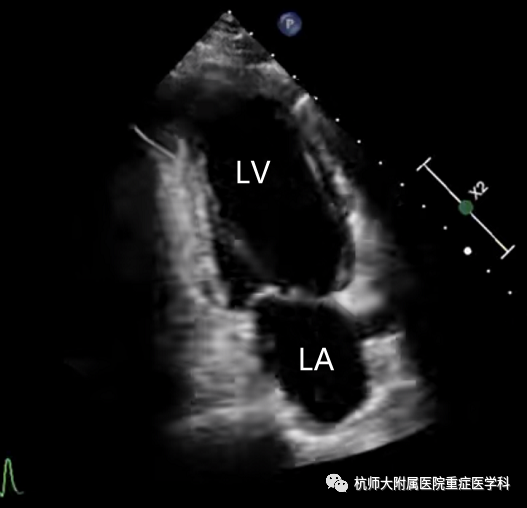

e.心尖两腔心切面:位置选择:心尖处,超声探头声束朝向患者右肩方向指向心底;操作中在四腔心基础上,将超声探头逆时针旋转60°~90°,可出现两腔心切面。

主要评估内容:(1)作为评估二尖瓣的补充切面;(2)作为四腔心的补充切面一起测量左心室射血分数及评估室壁运动。